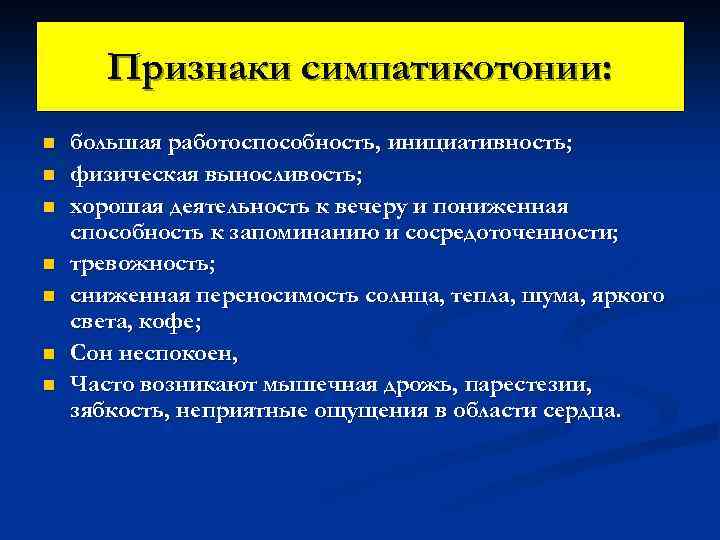

Признаки симпатикотонии: n n n n большая работоспособность, инициативность; физическая выносливость; хорошая деятельность к вечеру и пониженная способность к запоминанию и сосредоточенности; тревожность; сниженная переносимость солнца, тепла, шума, яркого света, кофе; Сон неспокоен, Часто возникают мышечная дрожь, парестезии, зябкость, неприятные ощущения в области сердца.